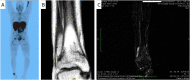

The present case report is aimed to highlight the difficulty and the reason for the delayed diagnosis of phosphaturic mesenchymal tumors, emphasizing the need of standardized protocols for diagnosis, surgery and follow-up in high-volume hospitals. The clinical signs and symptoms, diagnostic and therapeutic procedures, immunohistological features were analyzed. Delayed diagnosis of phosphaturic mesenchymal tumor was primarily due to non-specific clinical symptoms such as fatigue, muscular and bone pain, and multiple fractures. This cryptic clinical picture made the diagnosis tricky that led to treatment of patient for non-specific pain and stress fractures before to consider the tumor-induced osteomalacia syndrome. Some well-documented studies were found in the literature in which the history of trauma is a critical trigger of glomus tumors. Extra-subungual tumors most frequently occur in the knee and ankle regions, particularly among young adults, and the diagnosis is typically made approximately 7.2 years after initial symptom onset. The difficult tumor localization represented an additional obstacle to the prompt treatment, leading to delayed curative surgery.